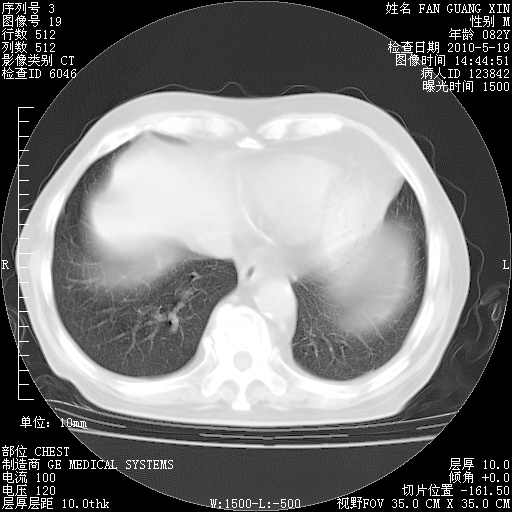

复查肺部CT,明显好转。为什么发热呢?

治疗3周后的肺部CT

治疗3周后的肺部CT纵隔窗